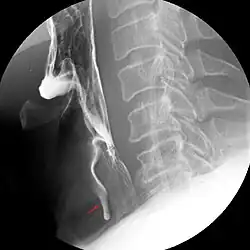

Aufmerksam sollten Anwesende werden, wenn es bei einer Person zu einer plötzlichen Hustenattacke kommt, die mit Atemnot einhergehen kann, aber nicht muss. Eine radiologische Untersuchung mittels Röntgen-Thoraxübersichtsaufnahme, Röntgen-Thoraxaufnahme in Exspiration oder einer Durchleuchtung sind erste diagnostische Maßnahmen. Eine Szintigraphie ist eine weitere Möglichkeit. Die Krypton-81-m-Ventilationsszintigraphie hat eine besonders hohe Detektionsrate. Schließlich sollte eine Bronchoskopie neben der diagnostischen Klärung auch den therapeutischen Erfolg bringen.